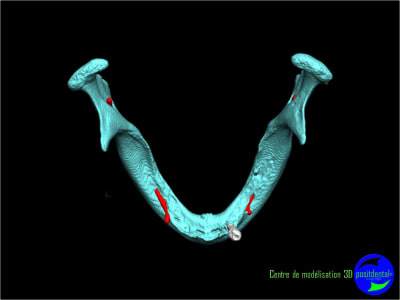

Il faut faire une ostéotomie en forme de tube au niveau de 33 et 43 et y placer deux tiges cylindro-coniques en titane. Quelques mois après tu pourras t'en servir pour fixer la prothèse.

Résorbée genre comme ça?